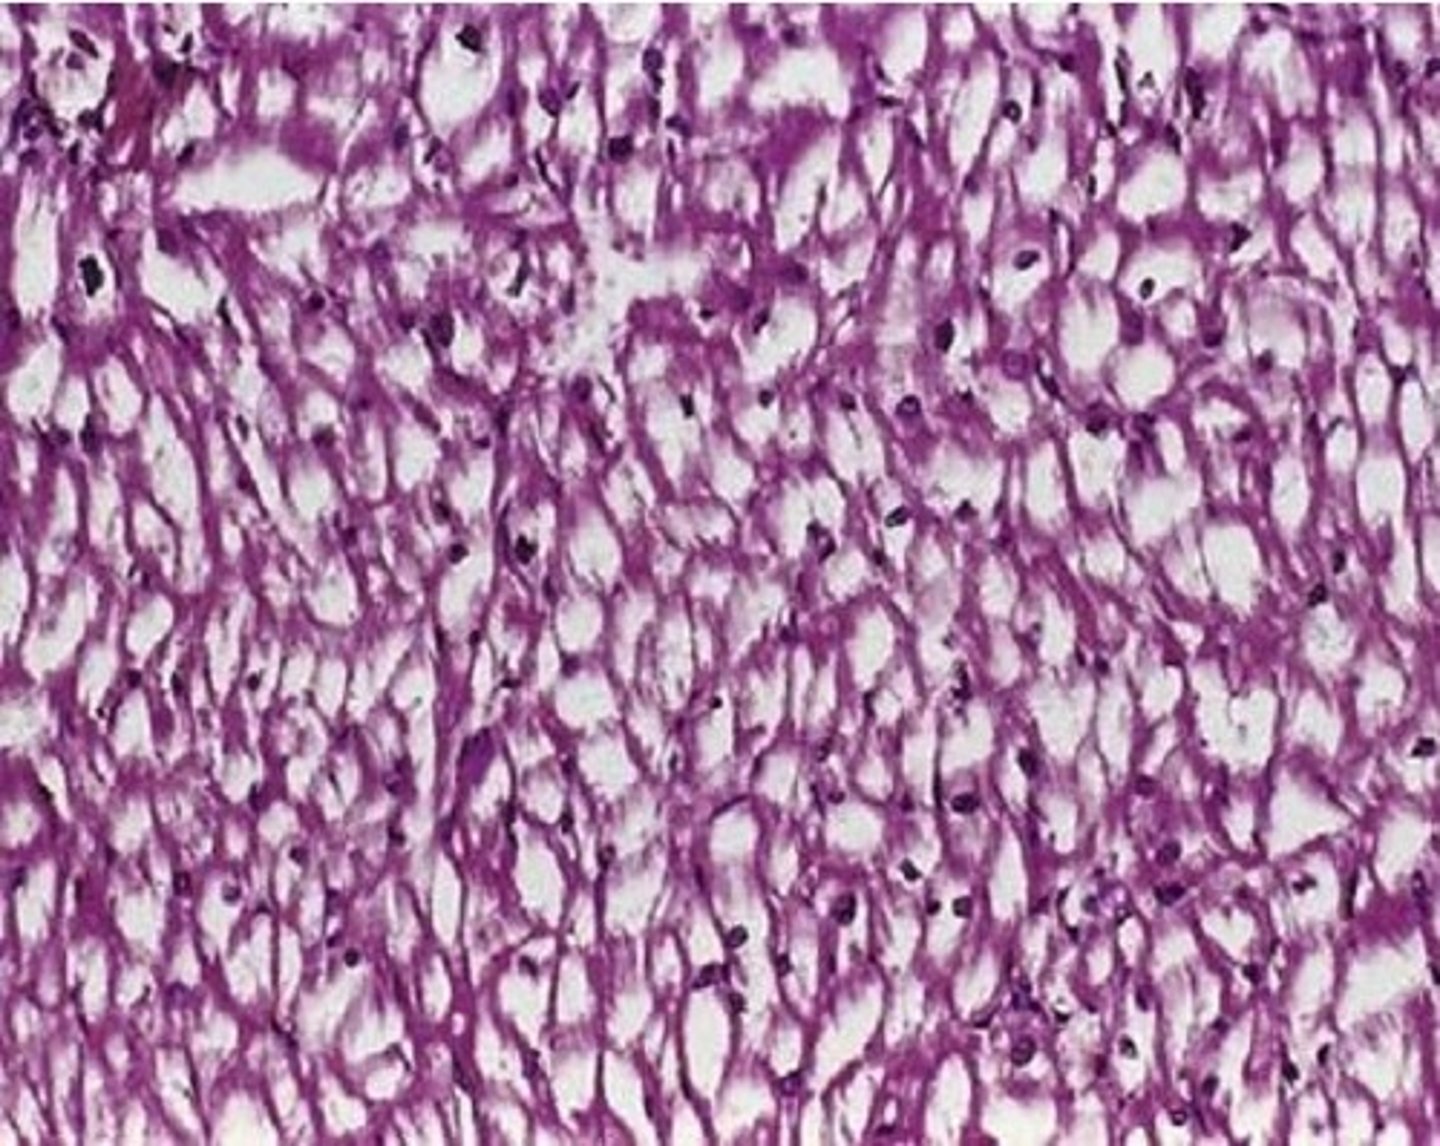

Dark purple skin/ mouth nodules in a patient with AIDs

Kaposi Sarcoma, associated with HHV-8

Endothelial cell tumor, not of blood vessels (will not blanche)

Spindle cells

Spreads via blood